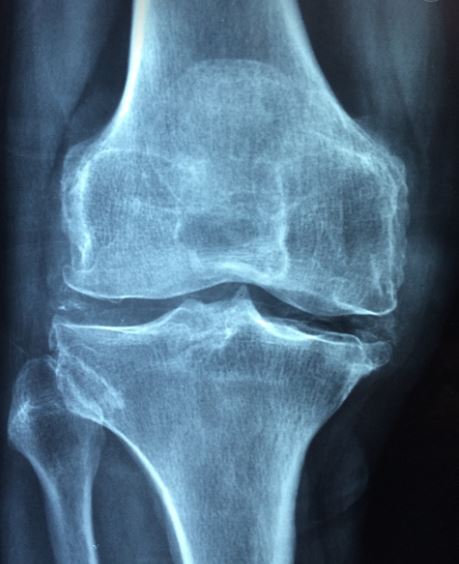

골다공증을 아시나요?

뼈의 주요 구성 성분인 칼슘이 빠져나가면서 골밀도가 낮아져

뼈가 약해지는 골다공증은 현대인들에게 너무 익숙한 질병중 하나 입니다.

골다공증의 증상은 초기에는 특별한 증상이 잘 나타나지 않기 때문에

정기적인 뼈밀도 검사를 통해 꾸준한 관리가 매우 중요 합니다.